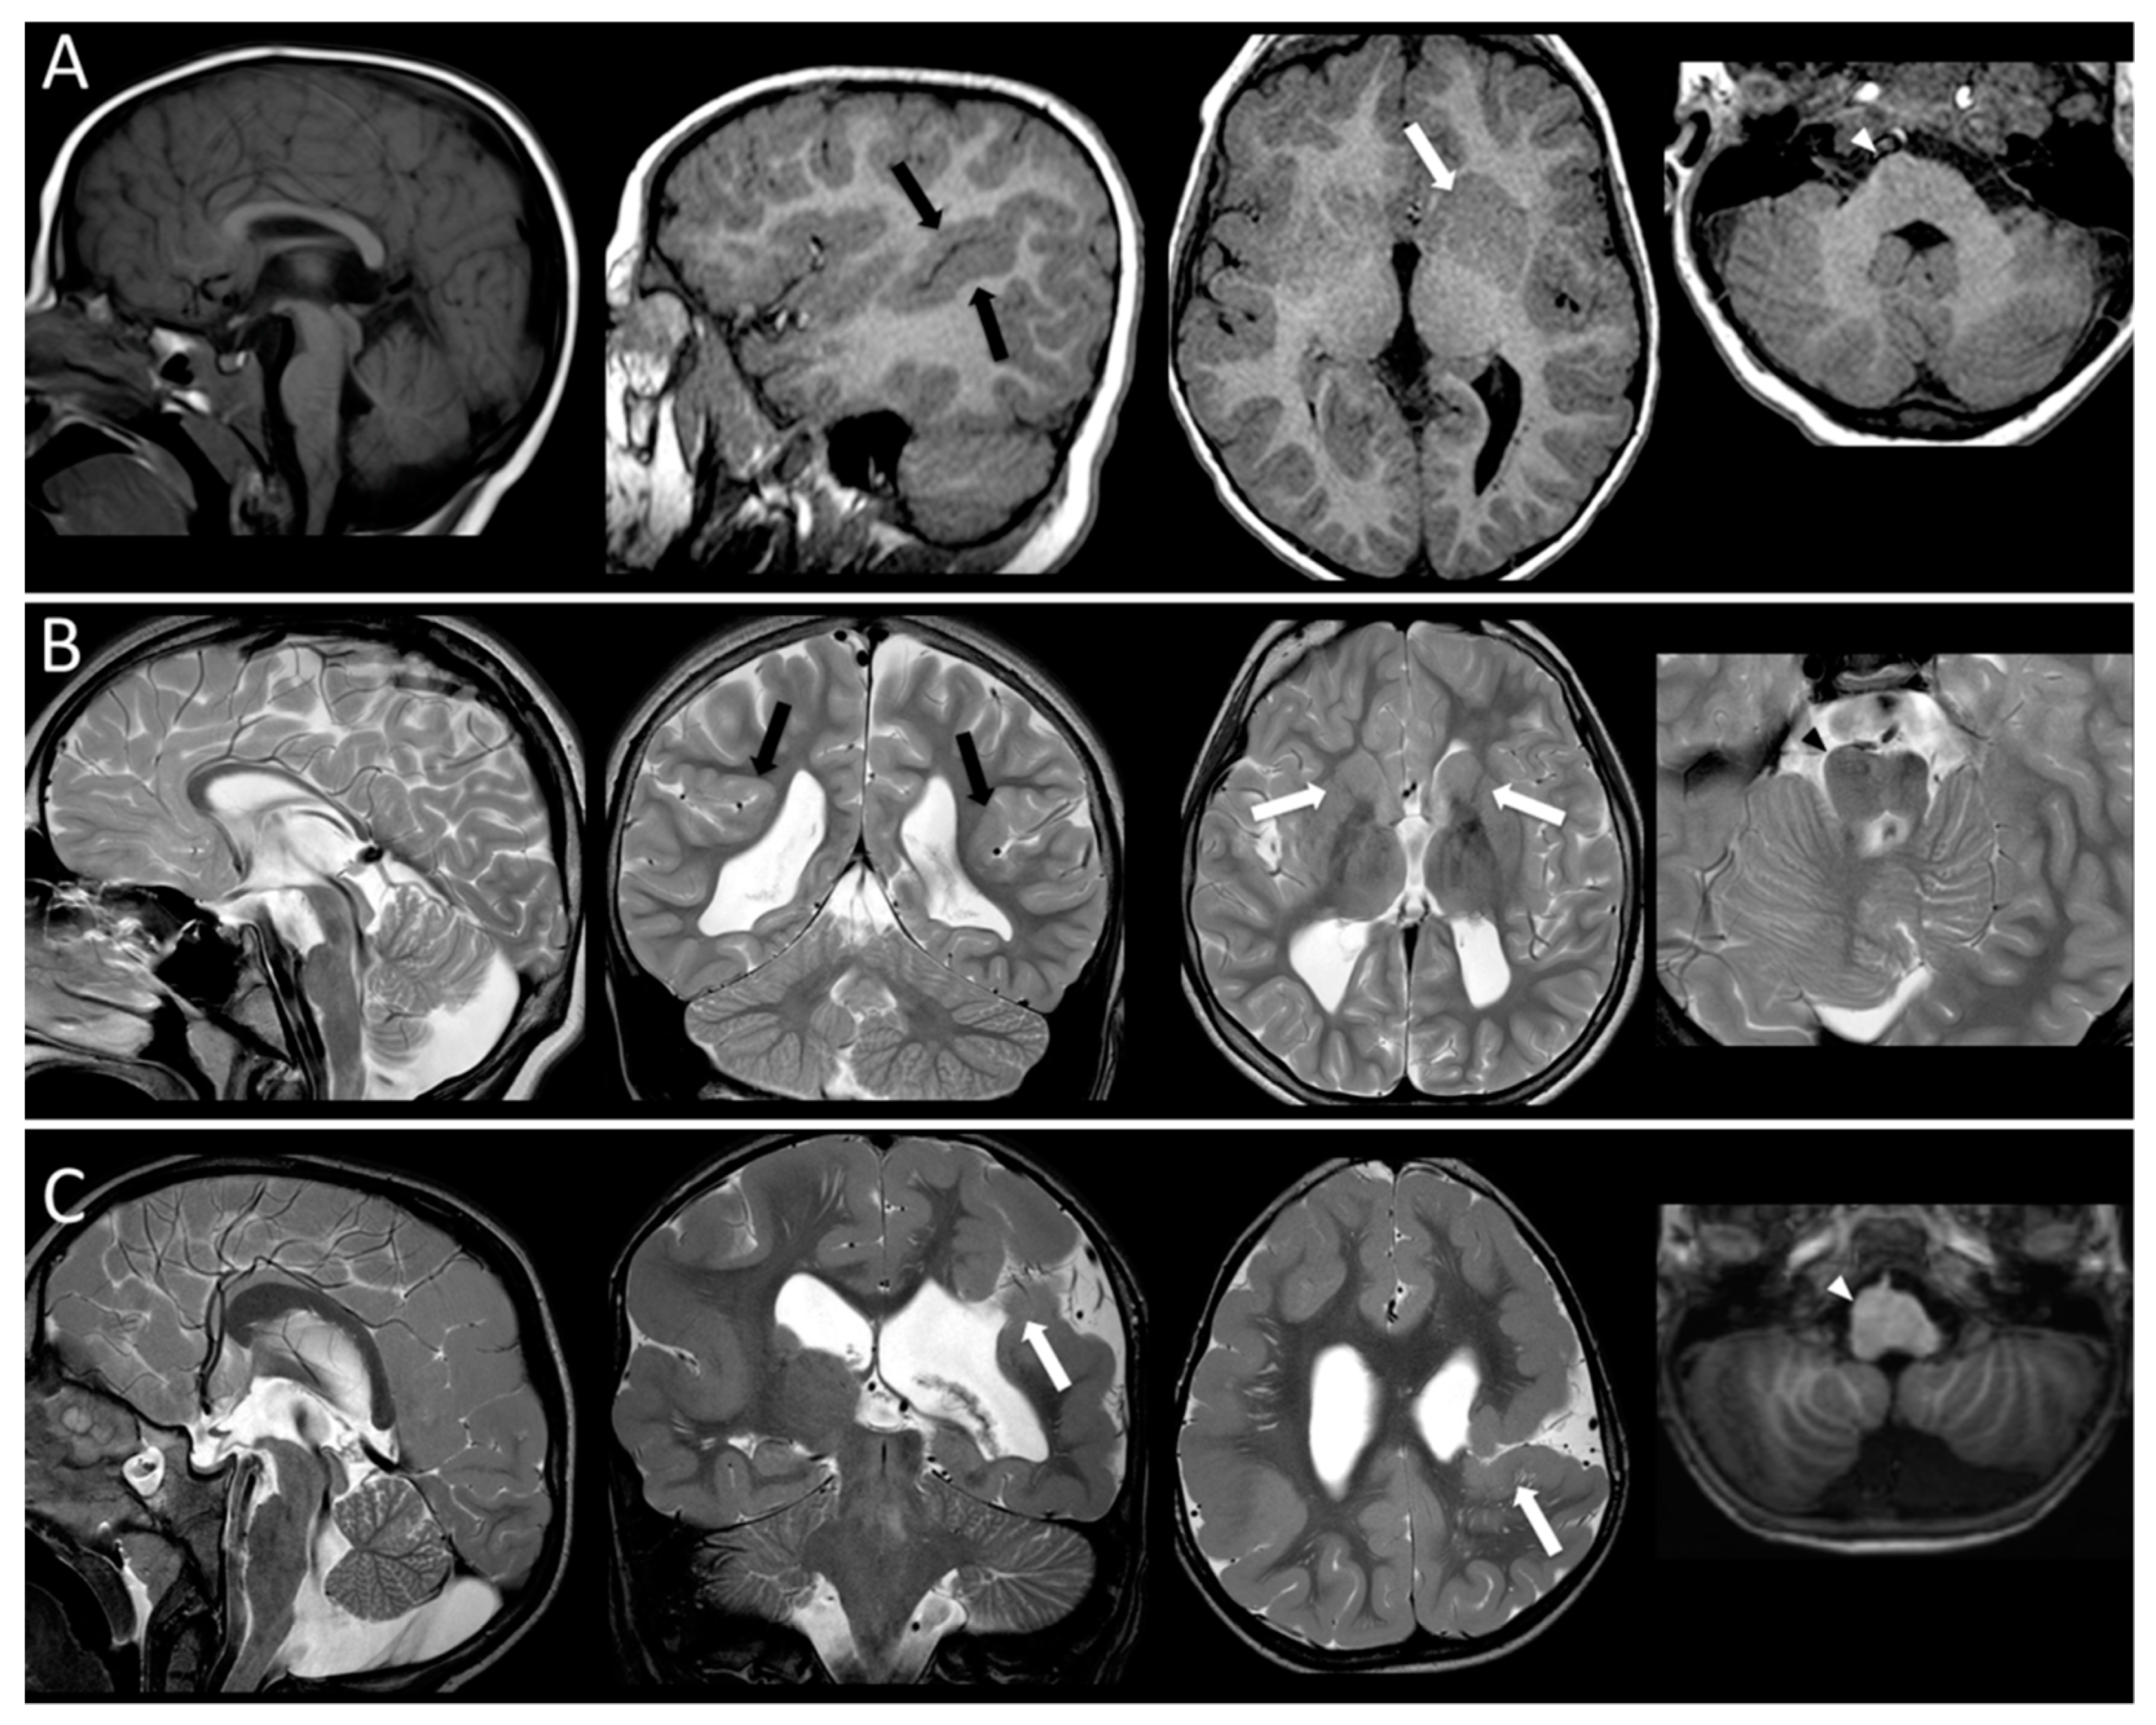

- Bahi-Buisson, N.; Poirier, K.; Fourniol, F.; Saillour, Y.; Valence, S.; Lebrun, N.; Lascelles, K. The wide spectrum of tubulinopathies: What are the key features for the diagnosis? Brain 2014, 137, 1676–1700. [Google Scholar] [CrossRef]